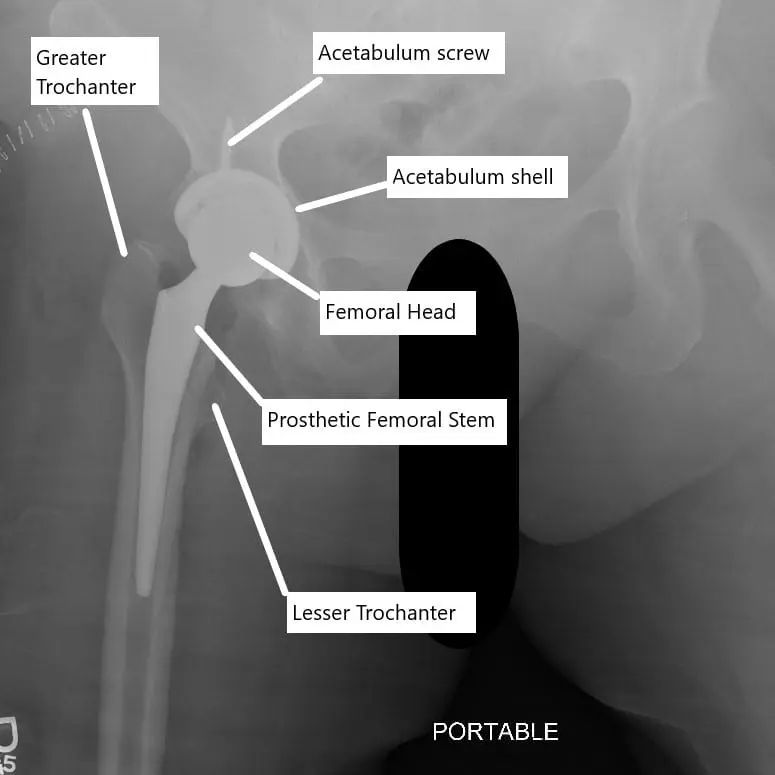

X-ray showing total hip replacement.

X-ray showing total hip replacement